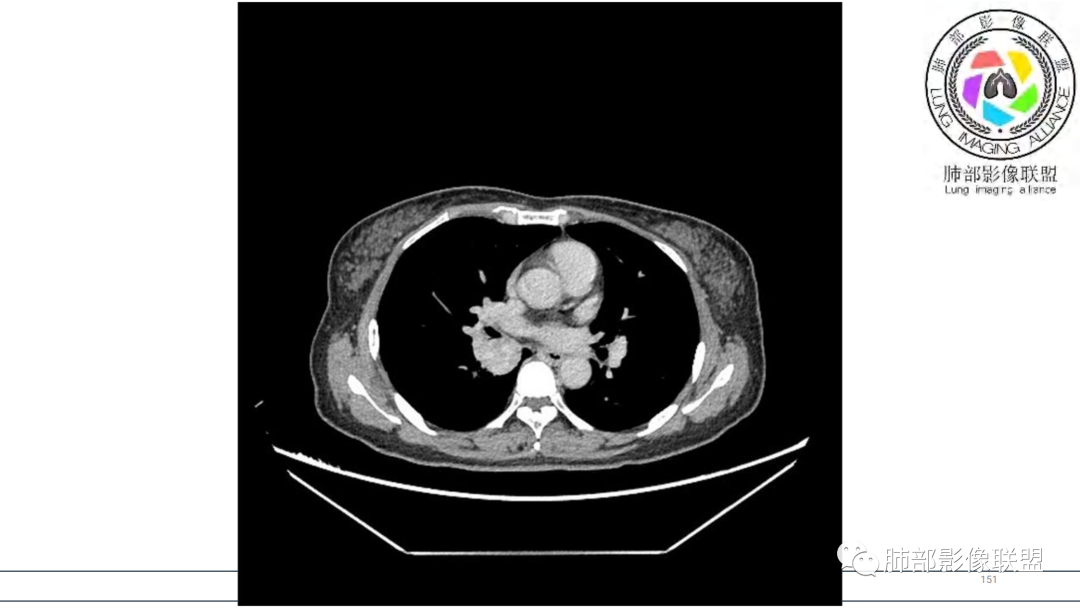

2.右肺下叶及中间段支气管后方类圆形块影,边界较清楚,未见分叶及毛刺,病灶部分突入支气管腔内(冰山一角),局部管腔狭窄,相应肺叶未见片影或体积变化。

3.块影密度均匀,未见液化坏死及钙化,渐进性强化,强化显著。

中青年女性,支气管管腔内外肿块(“冰山征”),边界较清楚,强化显著,未见阻塞性肺不张,尽管未出现“类癌综合征”临床表现,仍然符合典型类癌影像学表现。

类癌临床表现无特异性,影像学检查仍然是肺类癌的主要诊断依据。其特征性表现是孤立的、边界清楚的肿物,密度可均匀或不均匀,边缘多清楚锐利,部分病例可见浅分叶及毛刺。类癌侵及的支气管局部增厚,与正常的管壁分界清楚,局部呈乳头状突起,表面光滑。肺门旁肿块往往边缘光整、轮廓清楚、密度均匀,增强扫描大多呈均匀明显强化,可有持续强化或延迟强化。中央型肺类癌可引起支气管壁局限性增厚,形成轮廓光滑的管壁结节,并与腔外大病灶形成“冰山征”。少数病例可沿支气管腔内长轴生长,呈指套样改变,类似肺鳞癌,但较肺鳞癌血供丰富。